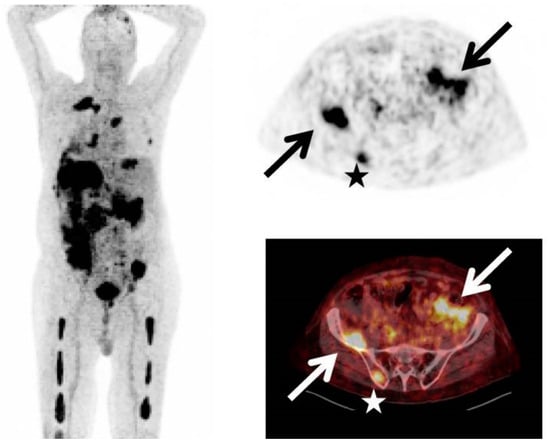

Evaluating the response to treatment is a significant area where [18F]FDG PET/CT might offer greater utility compared to conventional imaging methods [23] (Figure 4 and Figure 5). By analyzing the metabolic behavior in areas with clonal plasma cell growth, [18F]FDG PET/CT can precisely gauge and quantitatively measure alterations in cancer cell activity following therapeutic interventions [24,25,26,27,28,29]. Furthermore, there is a robust correlation between negative [18F]FDG PET/CT results and a highly positive response to treatment in myeloma patients [20].

Figure 4.

This figure presents the case of a 39-year-old patient with symptomatic multiple myeloma (MM) who was being prepared for high-dose therapy (HDT) and autologous stem cell transplantation (ASCT). This patient underwent an [18F]FDG PET/CT scan both before and after treatment. The maximum intensity projection (MIP) of the [18F]FDG PET/CT scan before treatment (A) revealed a combination of intense, widespread uptake in the axial skeleton and multiple focal bone marrow lesions in locations such as the sternum, ribs, humerus, scapula, and femur (indicated by arrows). The follow-up [18F]FDG PET/CT MIP after HDT and ASCT (B) demonstrated a complete remission of both the diffuse bone marrow uptake and the focal MM lesions. Figure 2, PMID: 31905752, PMCID: PMC6982887, OPEN ACCESS.

Figure 5.

This figure is displaying the baseline (A,B) and follow-up (C,D) [18F]FDG PET images of a patient with MM before high-dose chemotherapy and 2 months post-treatment. The [18F]FDG uptake by the lesions was quantified using an adaptive thresholding algorithm. The image was sourced from PMID: 31084773 (Figure 3), and permission was granted for its use.